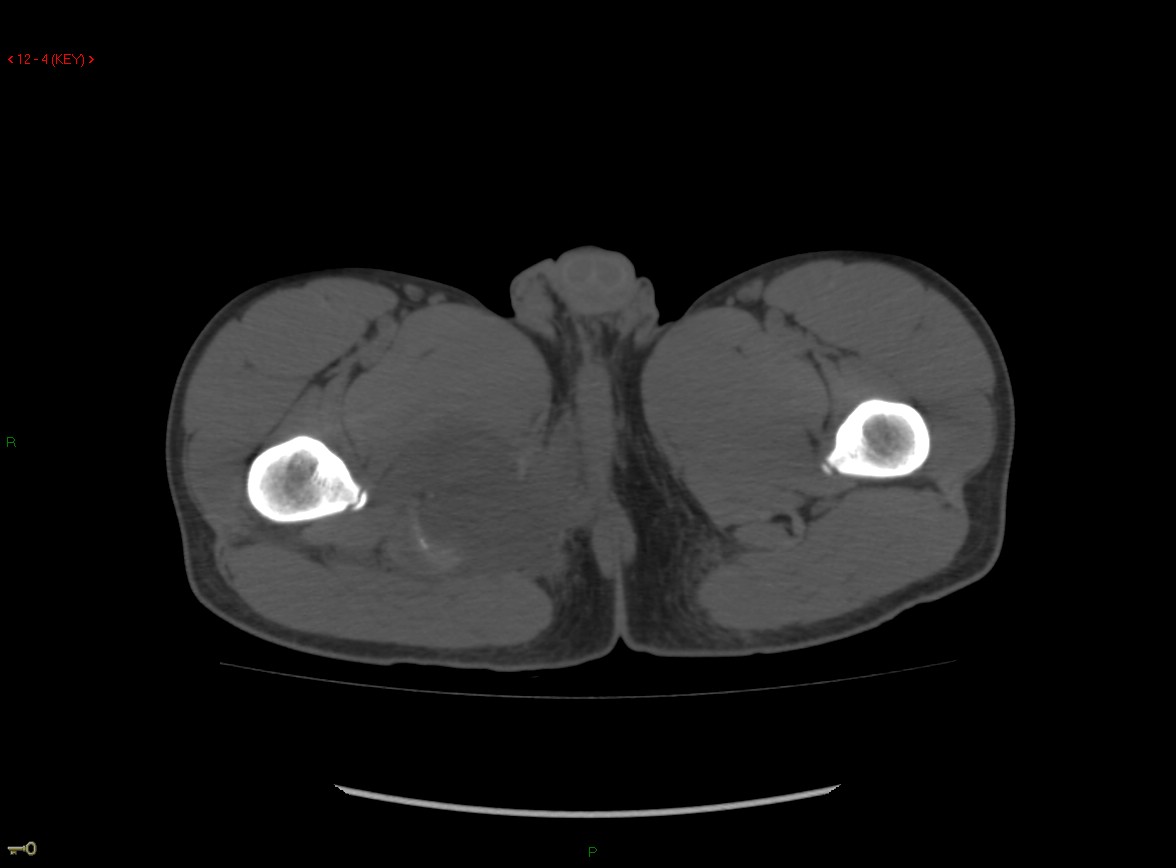

Figure 3 for case Ischial tuberosity ( RID2550 ) avulsion

Figure 3